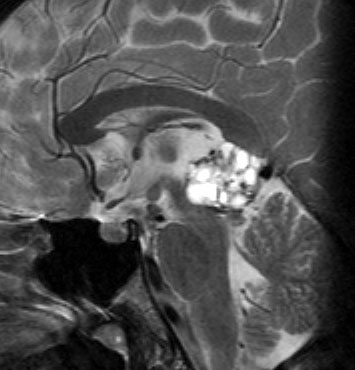

成人男性の松果体芽腫です。左のCTでは白く見える石灰化があります。水頭症があって頭痛と嘔吐で発症しました。右のMRIでは腫瘍の形が丸くなくて周囲の脳に浸潤したり脳室の壁などにべっとり広がっているように見えます。悪性腫瘍の特徴的な像で,開頭手術をしても摘出できないことが判ります。松果体芽腫は悪性度が高くて(WHOグレード4),脊髄などに播種転移したりしますし,手術だけでは治りません。

腫瘍は定位脳手術で生検をしました。水頭症に対しては内視鏡で第3脳室開窓術を行なって症状を改善しました。左のMRIで水頭症が良くなっているのが判ると思います。それから,全脳脊髄に30グレイの放射線治療をして腫瘍局所には24グレイの照射を追加しました。同時にICE化学療法というのを6コースしました。右のMRIでは治療が終わって小さく固まった残存腫瘍が見えます。この残存腫瘍は第3脳室の壁にくっついていて摘出するリスクがとても高いと思いましたので,そのままずーっと10年間様子を見ていますが再発していません。でも,残存腫瘍がなんとか取れる時は徹底的に取ってしまった方が再発率は少ないといえます。